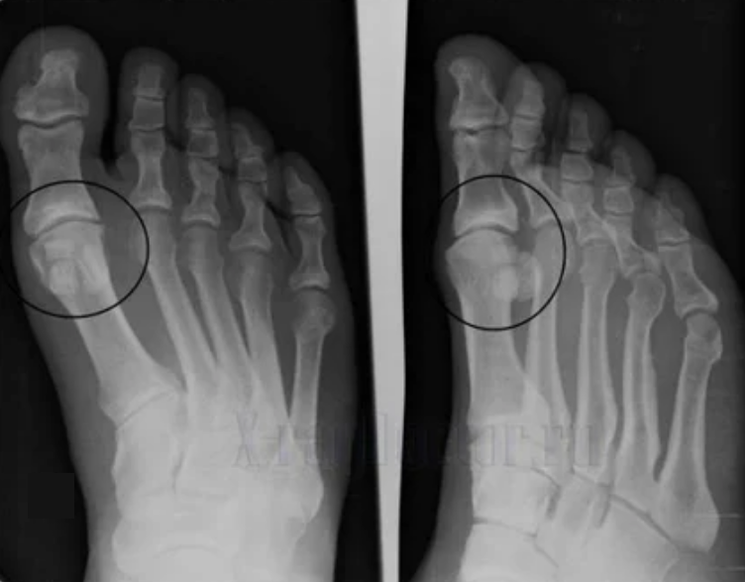

To make a diagnosis, rheumatologists study the patient's complaints and prescribe an X -Ray examination.Most often, radiography is used in 2 projections.The doctor looks at the presence of dystrophic disorders in the hyaline cartilage and bone joints.If the articular gap is reduced, the bones are deformed or flattened, there are cystic formations on the surface of the cartilage, osteophytes are visible signs of arthrosis.During inspection, arthritis indicates the instability of the joint: the limb axis and the subluxation is disturbed.

Often an X -Ray view is unable to provide complete information about the condition of the joint.For a more complete study, calculated tomography is described, is effective for bone examination.MRI is most often used to study soft tissue.